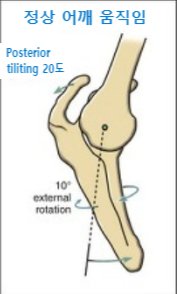

견갑골 운동장애의 치료는 크게 3가지입니다.

1. 견갑골의 후인(Retraction) 회복

2. 견갑골 뒤쪽 기울어짐(Posterior tilt) 회복

3. 외회전(ER)의 회복